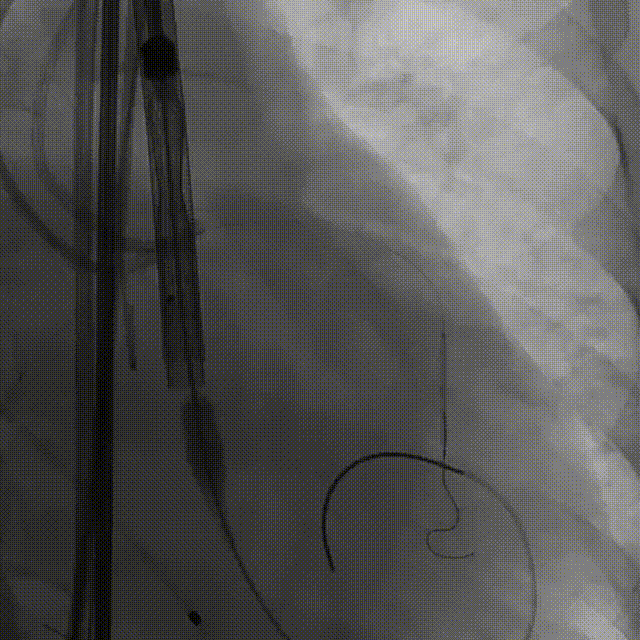

9. 工作位评估冠脉

10.右冠行烟囱支架技术

11.左冠造影评估灌注正常,

撤出支架